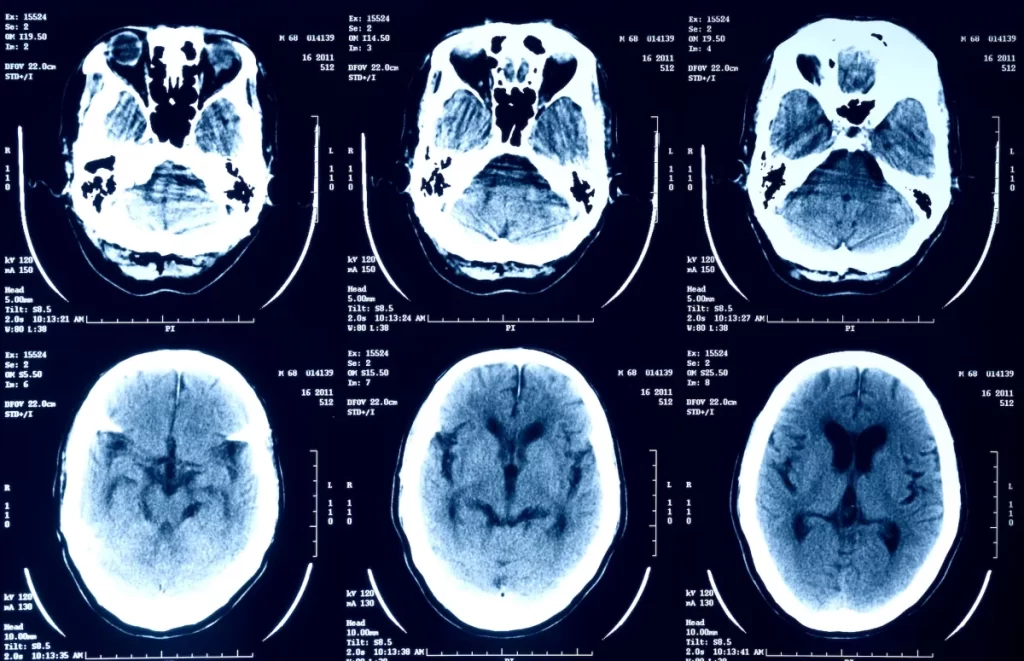

En la actualidad, la inteligencia artificial (IA) se está integrando cada vez más en nuestras vidas, proporcionando soluciones innovadoras en diversos campos, incluido el sector de la salud. Desde aplicaciones que interpretan resultados médicos hasta herramientas avanzadas que ayudan en diagnósticos, los chatbots de IA están demostrando su potencial para transformar el cuidado de la salud. Sin embargo, a pesar de sus beneficios, hay una creciente preocupación sobre la seguridad y la privacidad de los datos médicos. En particular, los usuarios que suben imágenes médicas, como radiografías, resonancias magnéticas (RM) y tomografías por emisión de positrones (PET), a plataformas de IA deben ser conscientes de los riesgos asociados con la protección de su información privada.

Recientemente, se ha observado que algunas plataformas están alentando a los usuarios a cargar imágenes médicas en sus chatbots de IA para que los algoritmos puedan interpretar los resultados. Un ejemplo es la plataforma X, anteriormente conocida como Twitter, que ha promovido la idea de que los usuarios suban sus radiografías y otros escaneos médicos al chatbot Grok. Sin embargo, este tipo de prácticas genera serias preocupaciones sobre la seguridad de los datos y la privacidad de la información personal.

Los chatbots de IA, como los de plataformas como OpenAI y X, generalmente utilizan los datos cargados por los usuarios para mejorar sus algoritmos y aumentar la precisión de sus respuestas. Sin embargo, este proceso puede tener implicaciones profundas para la privacidad. Al cargar imágenes médicas, como radiografías y resonancias magnéticas, los usuarios están contribuyendo directamente al entrenamiento de modelos de IA, lo que significa que sus datos podrían ser utilizados para otros fines sin su consentimiento explícito.